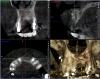

x3m Опубликовано 6 сентября, 2013 Автор Поделиться Опубликовано 6 сентября, 2013 (изменено) тест на витальность сейчас не проводился. мотивировать пациента не хочу - я рассказал свое видение ситуации.послушав авторитетные мнения, рассказал о вариантах на тему и прогнозах.дал ссылку на форум.написал письмо с вопросами автору установки имплантатов.созванивался и общался с этим же автором.как мне показалось, этого вполне достаточно, чтобы пациент самостоятельно принимал решение. теперь о вопросах.1. Где находится имплантат 16? Почему не видно кости?Визуально виден доступ в этой зоне: разрез от 14 до бугра по вершине а/о ...и торчащие заглушки. т.к. от доктора инфы я не получил, подозреваю открытый синус? меня смущает отсутствие кости у 16, реакция слизистой в гайморовой, положение платформы относительно 15 (с оглядкой на будущее протезирование), габариты будущей коронки на 16 (КТ в окклюзии). 2. наличие кортикалки вестибулярно у имплантата в позиции 15 - где она? 3. Четвертый сегмент. 45 и 46-й платформами находились над силизистой.В этот визит проводилось протезирование 4 сегмента.насколько я понял, протезирование (+44 консоль) - временное (пластмассовая облицовка), хотя... для чего оно здесь? вероятно, оно-таки постоянное (пациент не знает, доктор информацию не раскрыл)). Коронки - массивные нависающие края (2-3мм вглубь при зондировании микрорезьбы), формат коронок с отрицательным углом, под балконом - отложения налета, легко кровоточащая десна... еще смущает глубина погружения имплантатов вестибулярно - кмк, в кости лишь половина макрорезьбы... какой прогноз? фото пока выложить не могу, постараюсь на след.неделе. 4. второй сегмент.Что делаем с 27,28? Думается, удаление 27,28 и откр. синус.реакция в гайморовой - затёк из кармана? 5. 36. несколько смущает ось и погружение.хотя изо всего установленного это самый неплохой)) 6. Состояние во фронтальном участке после костной пластики.материал не там, где хотелось бы.остатки под носовым ходом (красным), объема ни вестибулярно, ни по высоте нет.автор предложил имплантацию в этой зоне не рассматривать.Линия улыбки, в принципе, невысокая, но не хочется, чтобы перегружали 11 и 23 мостом с розовой керамикой... Какова вероятность восстановления объема аутоблоками?(желтым указана небная кортикалка). Коллеги, буду благодарен за попунктовые ответы п.с. сорри за много букоФ и картинкоФ Изменено 6 сентября, 2013 пользователем x3m Ссылка на комментарий

kriokov Опубликовано 6 сентября, 2013 Поделиться Опубликовано 6 сентября, 2013 похоже по кт, что винт 15 вестибулярно закрутили, и кортикалки там и не будет. Синус почти тотально со снижением пневматизации, чего там полипоз или полипоз и жидкость х\з. По поводу 16- похоже на открытый синус, но графт как то не плотно, и винт похоже только 2 мм за нативную кость цепляется. имхо. Странно, что оператор обьясниться не хочет, у всех косяки бывают, Ссылка на комментарий

Bier Опубликовано 12 сентября, 2013 Поделиться Опубликовано 12 сентября, 2013 1. имплантат 16з стоит своей частью в полости пазухи, выполнен синуслифтинг. Вокруг имплантата виден остеотропный материал слабо рентген контрастный. Своей коронарной частью имплантат стоит в мягких тканях на 4 мм, что делает прогноз на его дальнейшую жизнь сомнительным. 2. имплантат 15 з расположен слишком вестибулярно, кортикальная пластинка либо очень тонкая либо ее нет. Прогноз неблагоприятный.3. Необходимо как минимум перепротезирование. Прогноз оценивать исходя из наличия или отсутствия гноетечения и стабильности имплантатов. Возможно можно ограничиться увеличением ЗКПД и адекватным протезированием. При наличии гнойного перимплантита рекомендовано удаление. Прогноз сомнительный.4.Согласен, удаляем. Реакция в гайморовой может быть и от кармана, а может быть остаточными являениями. Не критичны для синуслифтинга.5.36I я бы сохранил.6.объем кости для имплантации неадекватный. Для восстановления аутоблоки прогноз сомнительный. Я выступаю либо за грамотновыполненный GBR либо за 3D по Кюри. 2 Ссылка на комментарий

x3m Опубликовано 18 сентября, 2013 Автор Поделиться Опубликовано 18 сентября, 2013 (изменено) протоколирование перед удалением:Алле- -АП! "Удалить за 0,60 сек.": - только что из лунки. на поверхности гной, ошметки кости и чуть свежей крови - видимо, не прижился ... кюретаж, губка в лунку, диплен сверху: ...и рентгенконтроль:смутило наложение тени на пульповую камеру (хочется, чтобы это была костная тень, а не дефект корня с перфорацией). Через 3 дня:подтверждение перфорации (инструменты не цепляют по дистальной стенке, ашка не уперлась ни во что и проскочила почти до апекса): При конденсации кальций тоже не вышел за канал (уф, полегчало): пока 3.3 решили не удалять, наблюдаем. Вопрос по клыку:какой прогноз и какие действия? да, меня вот еще что "несколько смущает" в 4 сегменте:состояние имплантатов в позиции 4.5, 4.6 после установки (апрель с.г.):вид сейчас: МК, шатающийся Clip F в шахте, обратный угол коронок с поднутрением (на фото - зондируем резьбу), там налет и легко кровоточит, язычно над десной - полированная шейка имплантата.а на КТ имплантат 45 в кости на 4мм вестибулярно...как это может работать в долгосрочном прогнозе??? Изменено 18 сентября, 2013 пользователем x3m Ссылка на комментарий